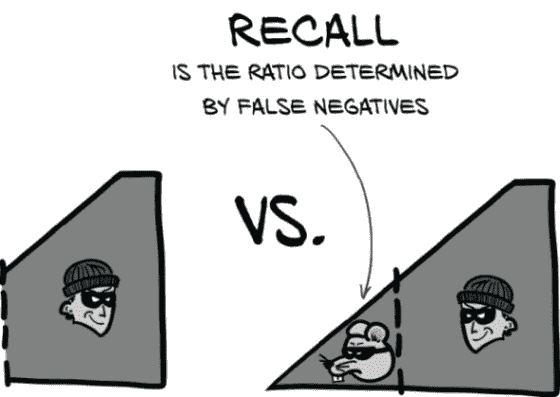

12.3.1 召回率是罗克西的优势

召回率基本上是“确保你永远不会错过任何有趣的事件!”正式地说,召回率是真阳性与真阳性和假阴性的并集的比率。我们可以在图 12.6 中看到这一点。

图 12.6 召回率是真阳性与真阳性和假阴性的并集的比率。高召回率可以最小化假阴性。

注 在某些情境中,召回率被称为敏感性。

为了提高召回率,要尽量减少假阴性。在看门狗的术语中,这意味着如果你不确定,就叫一声,以防万一。不要让任何啮齿动物小偷在你的监视下溜走!